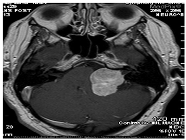

| Image | Category | Generated and Ground Truth Questions |

|---|---|---|

![]() | Modality | was this mri taken with or without contrast? which ventricle is compressed by the t2-hyperintense? was this mri taken with or without contrast? |